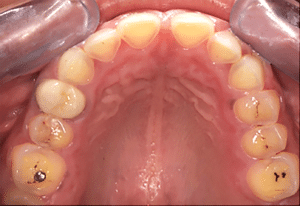

Mme AB vient en consultation pour deux raisons. La première est une douleur intense à chaque fois qu’elle boit ou mange froid. La deuxième est l’apparence de son sourire. Elle trouve que ses dents ont « raccourci » et qu’elles « s’effritent ». C’est devenu un complexe handicapant. À L’examen clinique on observe (Fig.1a, b, c, d, e) une usure vestibulaire de toutes les dents : plus prononcée au maxillaire et assez légère sur les incisives mandibulaires, une classe III canine et molaire droite, une classe I canine et molaire gauche avec une légère déviation des milieux et une usure importante des faces palatines du bloc IC maxillaire ainsi que des faces occlusales de 16 et 26. On constate aussi que les faces occlusales des autres dents sont moins touchées en apparence. On observe que les amalgames de 36 et 48 sont en relief par rapport à la dent support. Il est raisonnable de supposer qu’à l’origine ils devaient obturer une cavité et donc être à l’intérieur de la dent. Ceci témoigne donc aussi d’une forte usure sur 36 et 46. On observe enfin que les courbes de Spee sont complètement plates.

Fig.1a, b, c, d, e : Examen clinique.

Fig.1b.

Fig.1c.

Fig.1d.

Fig.1e.